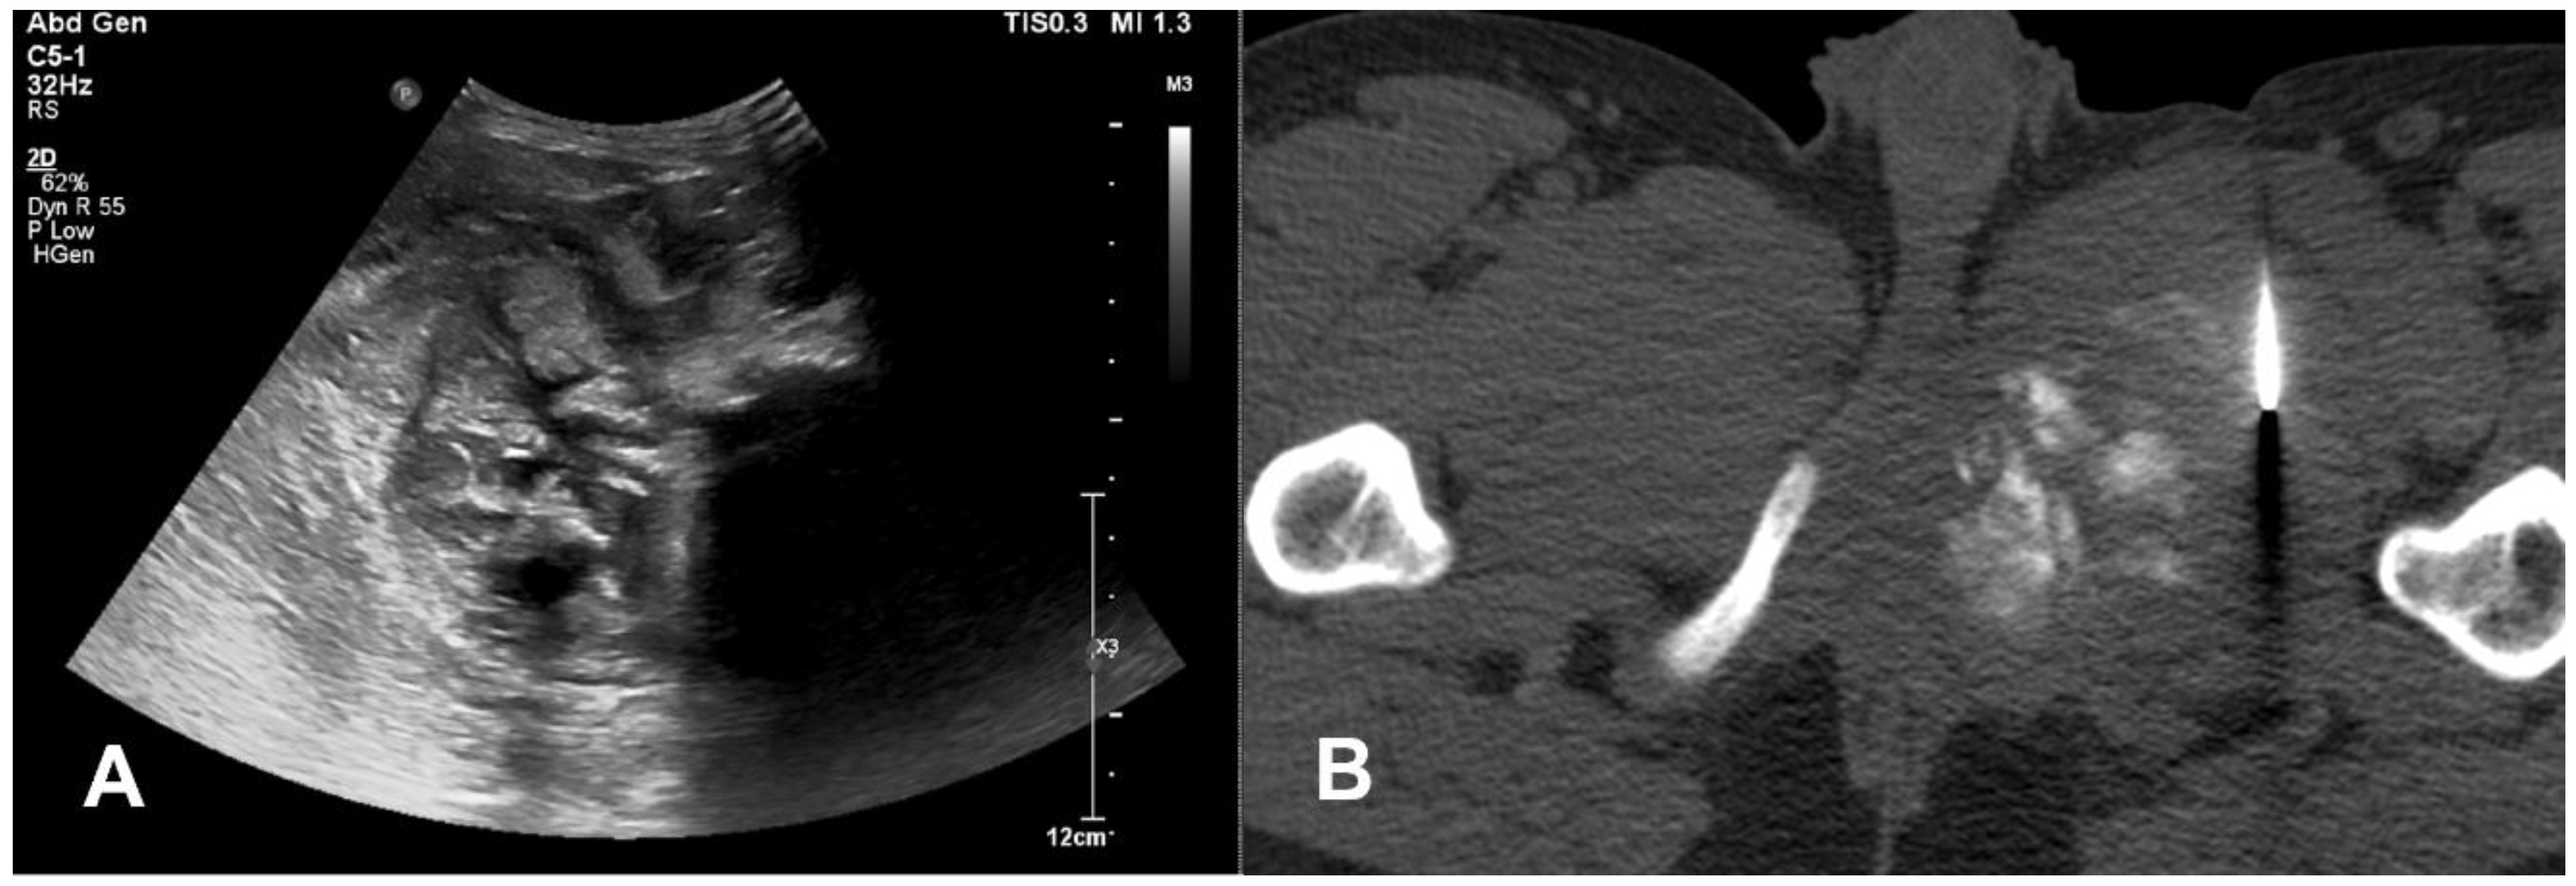

3.1.3. Teleangectatic Osteosarcoma

- Sangle, N.A.; Layfield, L.J. Telangiectatic Osteosarcoma. Arch. Pathol. Lab. Med. 2012, 136, 572–576. [Google Scholar] [CrossRef] [PubMed]

- Angelini, A.; Mavrogenis, A.F.; Trovarelli, G.; Ferrari, S.; Picci, P.; Ruggieri, P. Telangiectatic Osteosarcoma: A Review of 87 Cases. J. Cancer Res. Clin. Oncol. 2016, 142, 2197–2207. [Google Scholar] [CrossRef] [PubMed]